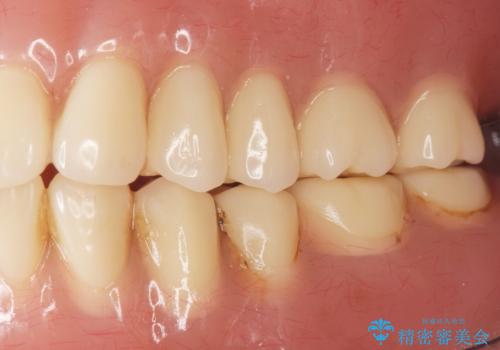

「ぴったりしていて全然はずれません!」と喜んで下さいました。

古い入れ歯は人工歯がすり減っており左右均等に咬むことができなかったそうですが、新しい入れ歯だと両側でしっかり咬むことができるとご満足頂けました。